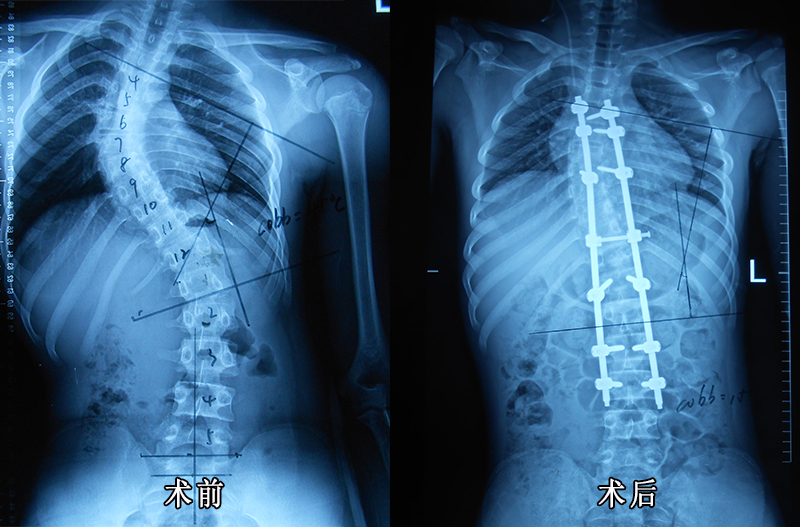

后路手术矫形治疗青少年特发性脊柱侧凸畸形附图片资料